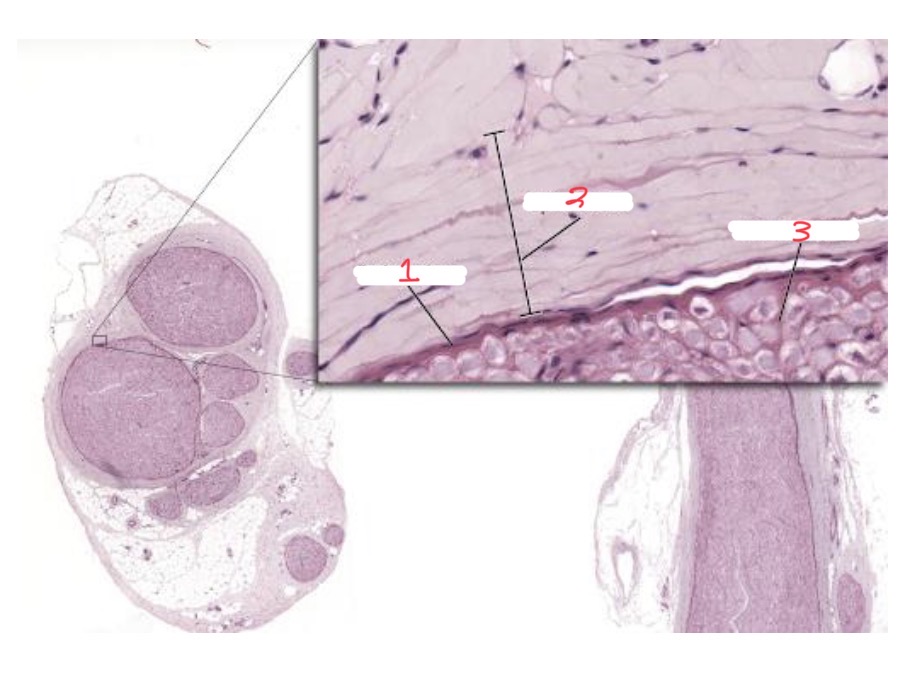

Peripheral nerve coverings

1

Perineurium

2

Epineurium

3

Endoneurium

Schwann cell

Myelin sheath

Axon